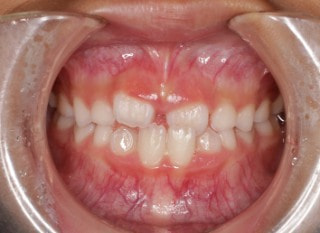

小児期の第二段階

終了時